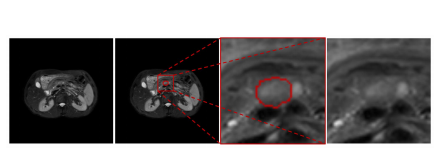

Fig. 1. Example of MRI pancreatic cancer. The two images on the left are entire original images, whereas the two images on the right are enlarged regions. The cancer is closely surrounded by other tissues that have a similar intensity, and the boundary is unclear

图1. MRI胰腺癌的例子。左边的两幅图像是完整的原始图像,而右边的两幅图像是放大的区域。癌症被其他具有相似强度的组织紧密包围,且边界不清晰。